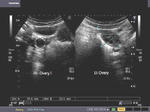

Hemorrhagic cyst of ovary

This young adult female patient underwent sonography of the ovaries. Upper Left image shows a cystic mass with multiple thin septae, in the left ovary. Power Doppler image (upper-right) of the left ovary shows no vascularity within the septae. Transvaginal ultrasound imaging of the ovary shows (bottom -Left) thin septae with clear fluid within the cyst. Smaller cystic lesion, appears to be a coexisting functional cyst of the ovary. Power Doppler image (lower right) confirms the findings described earlier. These ultrasound images suggest hemorrhagic cyst of the left ovary. Note the absence of solid tissue within the cystic lesion.